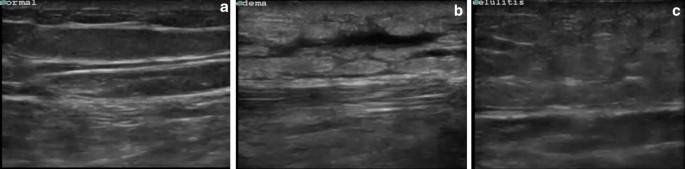

Dấu hiệu siêu âm của viêm mô tế bào bao gồm: lớp biểu-trung bì tăng độ dày, phản âm bất thường, mô dưới da cũng tăng âm, ranh giới giữa lớp biểu – trung bì và mô dưới da không rõ. Thường hữu ích khi so sánh vùng bình thường bên cạnh hoặc ở đối bên.

Sự tích tụ dần dần của phù nề trong mô dưới da tạo hình ảnh các dải dạng đường trống âm có phân nhánh tạo nên hình ảnh các thùy hay còn gọi là hình "đá cuội"(cobble-stone).

+ Hình ảnh này cũng có thể gặp ở các trạng thái phù nề khác

+ Sự hiện diện của da dày và phản âm bất thường bên trên sẽ nghiêng về viêm mô tế bào hơn là phù nề